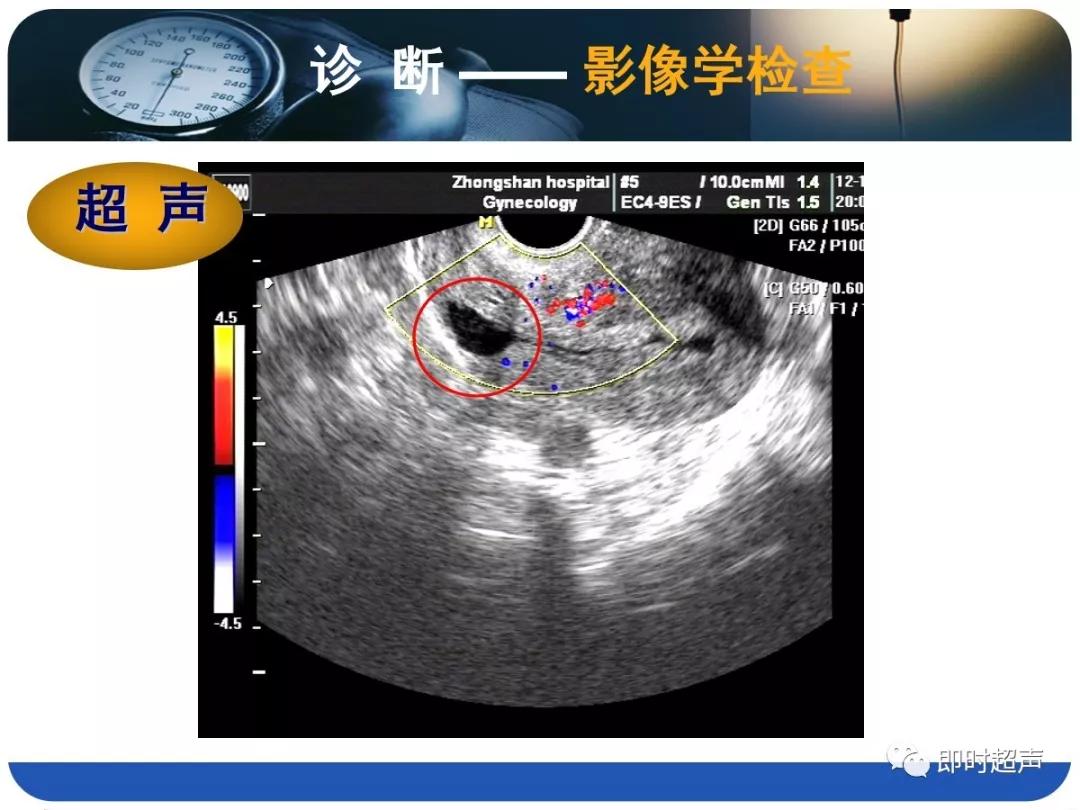

- 诊断主要依据病史(手术史)、临床表现(异常阴道流血)、检查结果(B超、HSG、宫腔镜等)综合判断。

- B超的特征性改变为:子宫下段或子宫峡部、宫颈管上段原剖宫产切口疤痕处肌层不连续,肌层内不规则液性暗区。